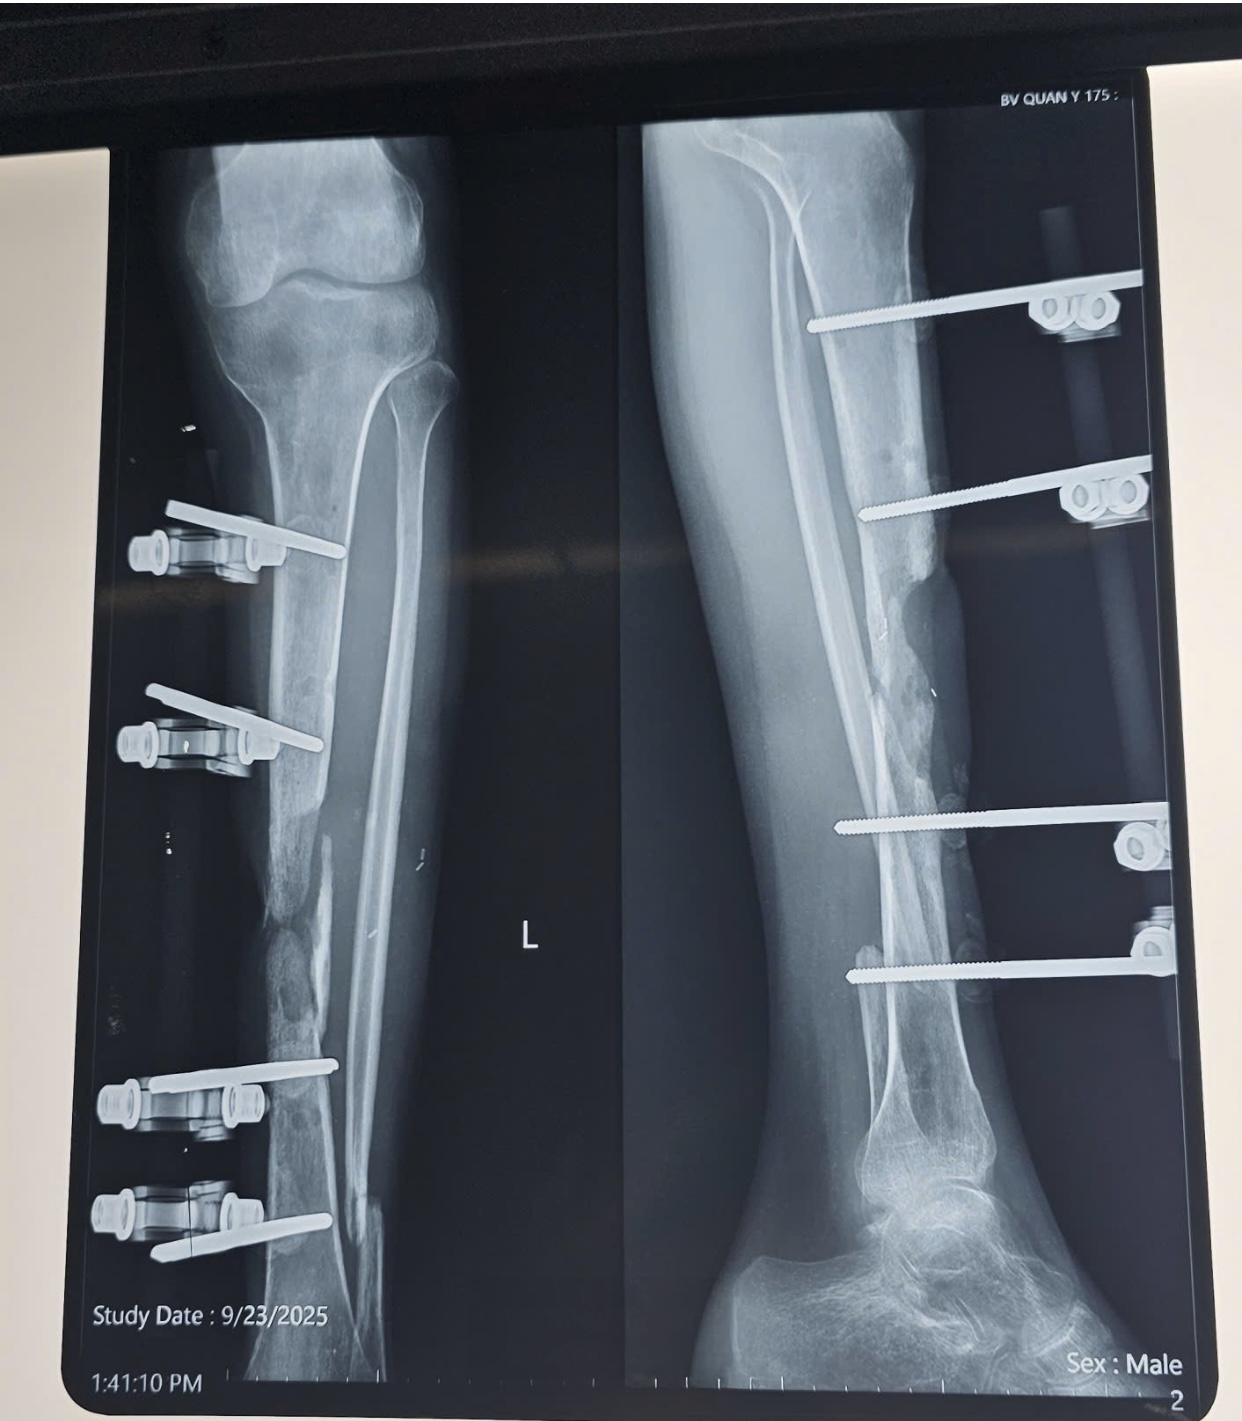

Nam bệnh nhân V.T.L (20 tuổi) bị gãy hở 2 xương cẳng chân trái đã được phẫu thuật đặt khung cố định ngoài, sau đó diễn biến viêm xương tủy xương điều trị nhiều đợt đến khi ổn định.

Ngày 23-9, anh L. nhập viện vào Khoa Bỏng và Vi phẫu tạo hình-Viện Chấn thương Chỉnh hình (Bệnh viện Quân y 175) trong tình trạng bị sẹo mổ cũ vùng trước xương chày xơ dính, còn khung cố định ngoài, khuyết xương chày khoảng 8 cm, gãy cũ xương mác trái, chân trái ngắn hơn chân phải khoảng 2 cm, không còn biểu hiện viêm hay nhiễm trùng.

Hình ảnh cho thấy bệnh nhân bị khuyết xương chày cẳng chân trái sau viêm xương tủy xương do gãy hở hai xương cẳng chân trái.

Sau thăm khám và hội chẩn, bệnh nhân được chẩn đoán: Khuyết xương chày cẳng chân trái sau viêm xương tủy xương do gãy hở hai xương cẳng chân trái năm thứ 2, còn khung cố định ngoài cẳng chân trái.

Sau 14 ngày phẫu thuật, vạt da hồng hào, siêu âm tại vùng nhận vạt mạch máu lưu thông tốt, đảm bảo vạt sống 100%, hình ảnh X-quang cho thấy xương thẳng trục, chiều dài 2 chân bằng nhau. Bệnh nhân hồi phục tốt, sinh hoạt bình thường, không có biến chứng sau mổ.